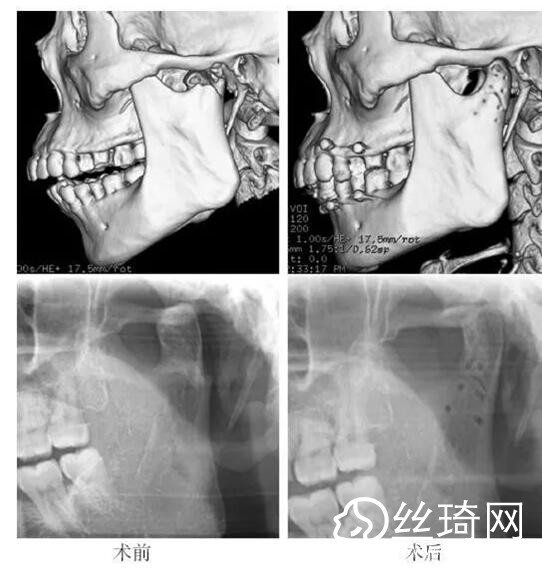

在106側(cè)中,髁突高位矢狀骨折46側(cè),中位髁頸骨折26側(cè),低位髁頸下骨折34側(cè)。髁突高位矢狀骨折及中位髁頸骨折均經(jīng)耳屏前徑路復(fù)位;34側(cè)低位髁頸下骨折中,經(jīng)耳屏前徑路復(fù)位13側(cè),頜下徑路復(fù)位19側(cè),頜后徑路復(fù)位1側(cè),穿腮腺徑路復(fù)位1側(cè)。髁突高位矢狀骨折復(fù)位后以1~2枚可吸收長螺釘固定(圖1)[3],采用的可吸收內(nèi)固定系統(tǒng)為BioSorb(ConMed Linvatec,芬蘭)、Inion OTPS(Inion,芬蘭);規(guī)格:直徑2 mm,長度15~20 mm。中位髁頸骨折及低位髁頸下骨折多以2塊可吸收板固定(圖2)[3],個別病例以1塊或3塊可吸收板固定,采用的可吸收內(nèi)固定系統(tǒng)為BioSorb(ConMed Linvatec,芬蘭)、Grand Fix(Gunze,日本)、Inion OTPS(Inion,芬蘭);規(guī)格:直4孔板,孔徑 mm或2.5 mm,長度21~35 mm,螺釘直徑 mm或2.5 mm,長度7~10 mm??晌蔗敯宓氖中g(shù)操作采用專用器械工具盒,并遵照廠家操作指引進(jìn)行。

82例髁突骨折患者,術(shù)后隨訪6個月至3年,平均年。所有患者術(shù)后未訴明X不適,面型基本對稱,面部肌肉運動正常,咬合對位良好,開口度~4.2 cm,平均(±)cm。3例患者開口型輕度偏斜,均為髁突高位骨折,其中2例為粉碎性骨折行骨折碎片摘除,1例為矢狀骨折,以可吸收螺釘固定后,創(chuàng)口感染,隨后行局部清創(chuàng)并取出髁突骨折片及可吸收螺釘,創(chuàng)口愈合良好。96側(cè)髁突骨折中,2例髁頸下骨折術(shù)后復(fù)查CT顯示輕度移位,但患者無功能障礙,持續(xù)觀察,未做特殊處理。其他患者未見明X排斥反應(yīng)及并發(fā)癥。